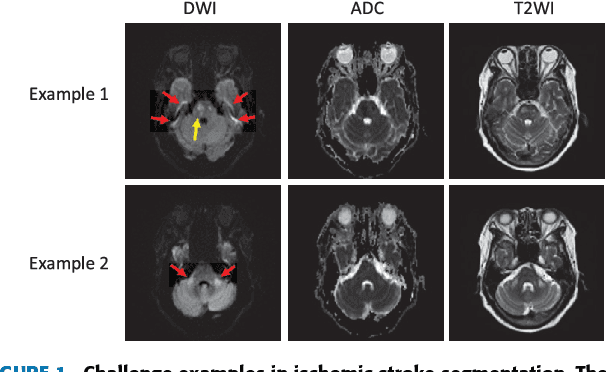

The patient with ischemic stroke can benefit most from the earliest possible definitive diagnosis. While the high quality medical resources are quite scarce across the globe, an automated diagnostic tool is expected in analyzing the magnetic resonance (MR) images to provide reference in clinical diagnosis. In this paper, we propose a deep learning method to automatically segment ischemic stroke lesions from multi-modal MR images. By using atrous convolution and global convolution network, our proposed residual-structured fully convolutional network (Res-FCN) is able to capture features from large receptive fields. The network architecture is validated on a large dataset of 212 clinically acquired multi-modal MR images, which is shown to achieve a mean dice coefficient of 0.645 with a mean number of false negative lesions of 1.515. The false negatives can reach a value that close to a common medical image doctor, making it exceptive for a real clinical application.